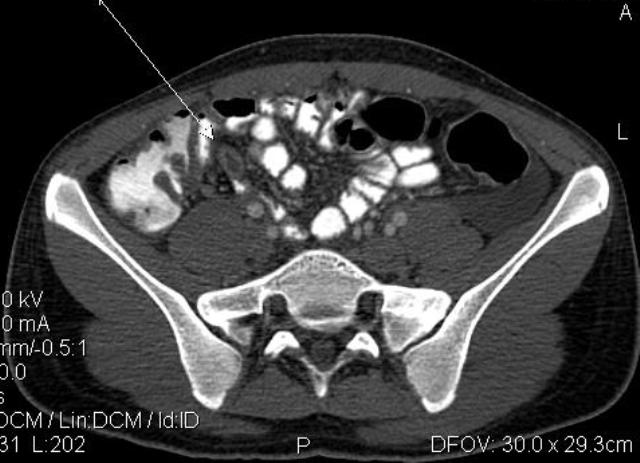

Диагностика острого аппендицита по УЗИ: очень актуальная тема; УЗ аппараты практически есть во всех клиниках; метод доступный и не сложный; главное владеть правильной техникой. Не буду загружать лишней теорией и разными ссылками; поделюсь практическим опытом. У меня линейный датчик 3-12 мегагерц с плавающей частотой; аппарат Филипс HD 11, всегда включаю соно-КТ (9800 цифровых каналов) и гармонику когда смотрю кишечник. Нормальный аппендикс видеть можно; но вопрос зачем??? Как правило, если при наличии достаточного опыта аппендикс не виден; значит скорей всего аппендицита нет. Когда "идешь" на аппендицит то главное по началу набраться терпения и......хорошая компрессия! По началу надо минут 10-15; потом когда появится достаточный опыт; за 2-5 минут можно справится и получить отличную визуализацию. Мочевой пузырь лучше опорожнить; часто он приподнимают тонкий кишечник и может закрыть "окно" через которое будет видно апендикс. Сначала находим слепую кишку потом находим илео-цекальное соединение;

после начинаем производить хорошую компрессию датчиком попрося пациента сообщить в какой точке боль наиболее выражена; медленными движениями датчика сканируем область наибольших болевых ощущений и как правило находим утолщенный отросток. Лучше начинать с поперечной визуализации и идти к верхушке аппендикса что бы убедится что это аппендикс и он заканчивается, а не тонкая кишка (которая если и закончится то только переходя в слепую); потом надо аккуратно развернуть продольно датчик и посмотреть от верхушки аппендикса к слепой. Норма диаметра: 3-4 мм; 5-6 мм под вопросом (клиника решает; но я в катаральный аппендицит не верю); 7-8 мм и больше, не компремируемый (фиксированный отросток)-острый аппендицит! Помимо наличие утолщенного аппендикса; признака "бычьего глаза" (bull-eye sign) при поперечном сканировании; надо обращать внимание на присуствие аппендоколитов в просвете; деструкцию стенки и свободной жидкости в зоне интереса.